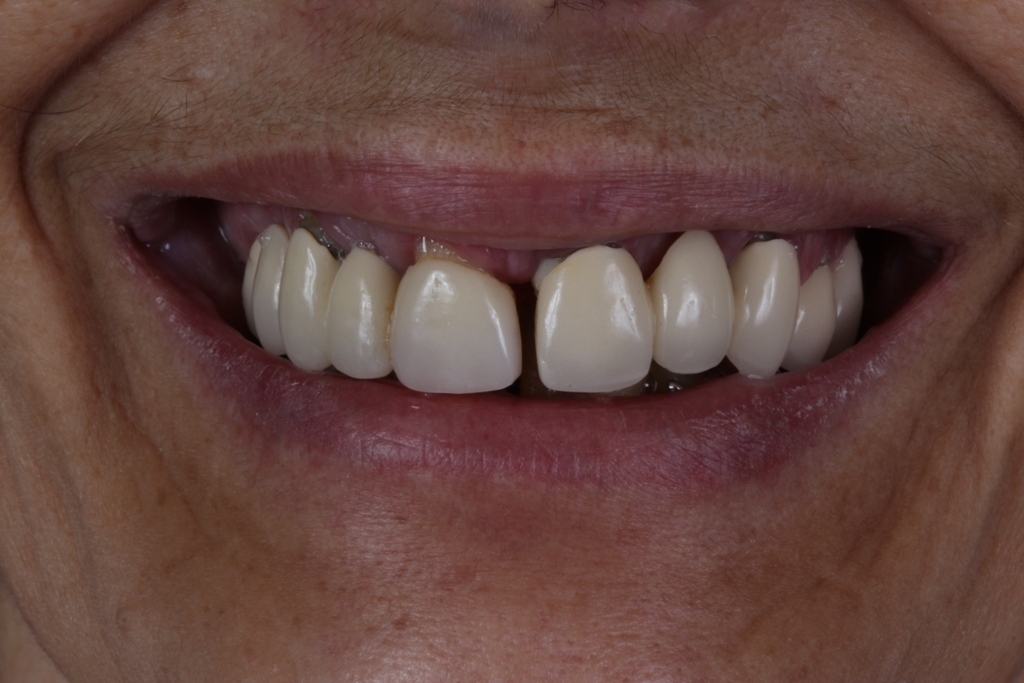

PRÓTESE TOTAL FIXA EM IMPLANTES

M.C.R.B.S.